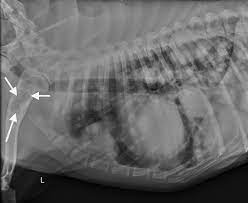

Department Of Surgery Liver Metastases from surgery.ucsf.edu The second kind of lung cancer in dogs is called metastatic lung cancer, which means the cancer originated somewhere else in the body, but has spread to the lung. The best way to increase a dog's prognosis against metastatic cancer is to be aware of the signs and to detect it early enough that treatment can be successful. Many owners choose to euthanize their pet to ease their suffering. Lung metastasis in dogs (and sometime it happens to cats, too) is a tough situation to experience. When the tumors have grown in size and made their way into the lymph nodes of your dog's lymphatic system, the prognosis is far lower, with the average survival time coming in at about two months. In this article we will help you understand the diagnosis of cancer in dogs. They can be detected on chest radiographs or computed tomography (ct) scanning. If, on the other hand, the dog has multiple tumors, or if the cancer has spread to the lymph nodes, the life expectancy is only about 2 months.

As best as you can, be attentive to your dog's breathing patterns, and protect it from exposure to second hand smoke. For small, solitary tumors that have not metastasized (spread), the average survival time with surgery alone is 20 months. If a dog is experiencing any serious respiratory symptoms or decline in their health, this is often a sign that the cancer is severe or it has spread to other parts of the body. In general, the prognosis for treating cases of metastatic cancer in dogs depends on how early the metastatic tumor is identified and how invasive it is. Following are some symptoms of end stage lung cancer in dogs and some tips for those who chose to provide their dog with some hospice care. End stage lung cancer in dogs will cause the. In this group, more than 50% are expected to live 1 year after the surgical removal of the mass. Pulmonary adenocarcinoma is cancer of the lungs, which can be primary (originates in the lungs) or secondary (originates somewhere else in the body), is a serious disease that can be fatal if not found and treated early. The lung is the most common location for metastatic osteosarcoma. Recovery of metastic neoplasia (cancer) in dogs unfortunately, the prognosis for metastatic neoplasia is grave due to the fact that the cancer has already spread. In this group, more than 50% are expected to live 1 year after the surgical removal of the mass. If, on the other hand, the dog has multiple tumors, or if the cancer has spread to the lymph nodes, the life expectancy is only about 2 months. Primary lung cancer, which is quite rare and metastatic lung cancer, spread from other areas of the body.

Holistic Vets Explain Natural Treatment Of Cancer In Dogs Dogs Naturally from www.dogsnaturallymagazine.com The average survival is closer to 8 months for dogs with big tumors, and 2 months if there is metastasis. In this group, more than 50% are expected to live 1 year after the surgical removal of the mass. The prognosis is generally good for dogs with primary lung cancer presenting with a single, small mass in their lungs that has not spread to the lymph nodes or other tissue. If a dog is experiencing any serious respiratory symptoms or decline in their health, this is often a sign that the cancer is severe or it has spread to other parts of the body. In general, the prognosis for treating cases of metastatic cancer in dogs depends on how early the metastatic tumor is identified and how invasive it is. You can spend a lot of money on invasive diagnostic tests like bronchoalveolar lavage … and never really know exactly what the cause is. Lung cancer in pets is rare. Our canine companions are a member of our family, making a cancer diagnosis extremely devastating.